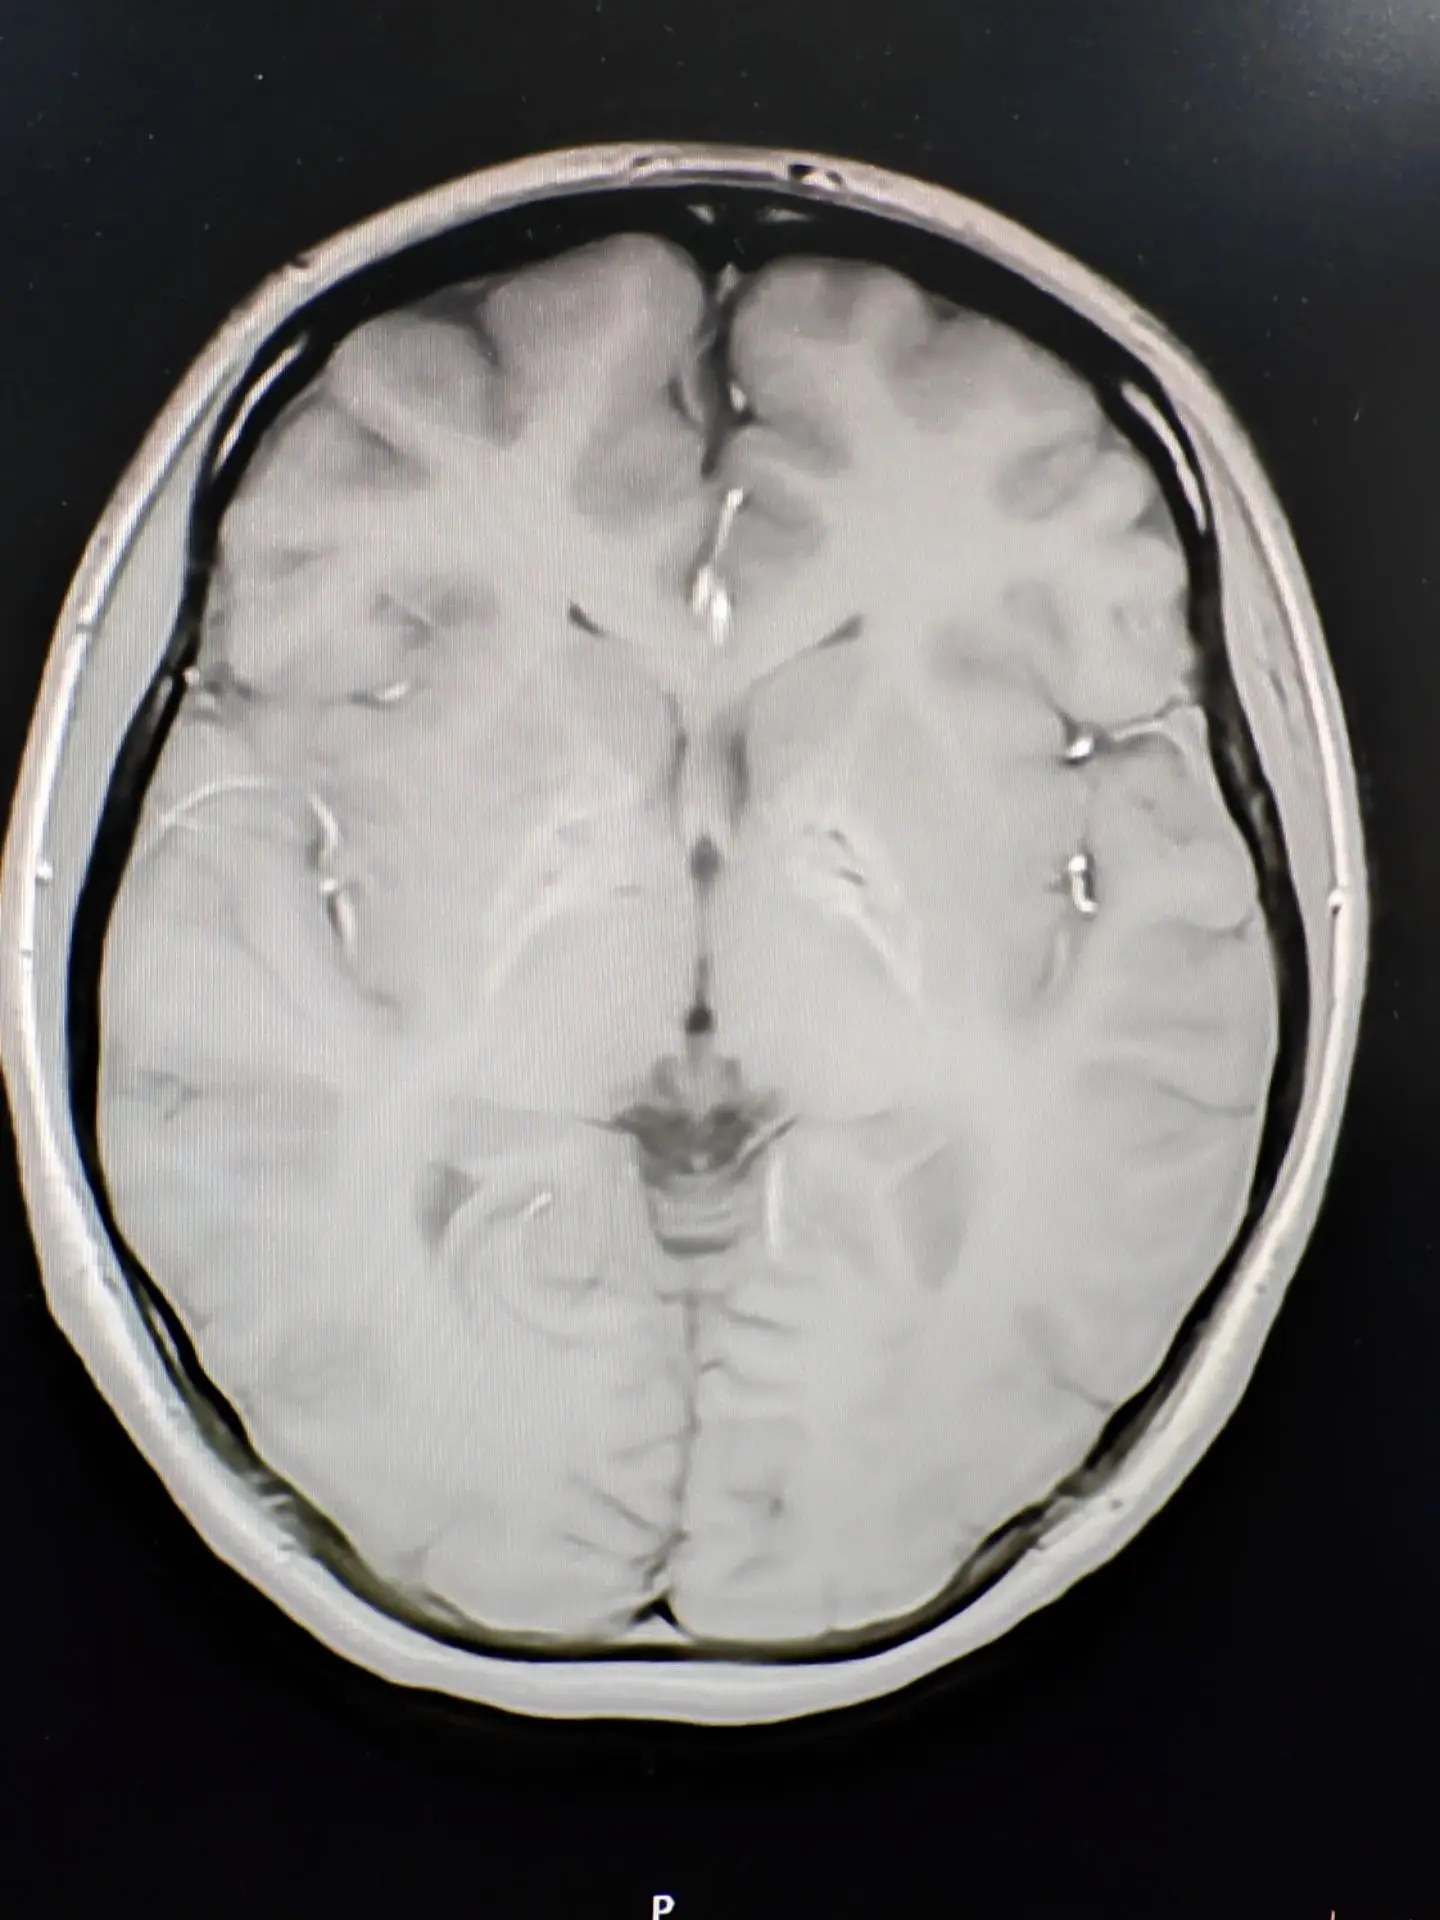

脑铁沉积病—虎眼征👁。脑铁沉积病目前发现有10种不同的基因遗传相关的神经系统退行性疾病,常伴有基底节区的铁沉积,其中有7种脑铁沉积病可表现为PPS。尤其最为常见的PANK2基因突变引起的泛酸激酶相关性神经退行性疾病,青少年起病,首发症状可表现为帕金森样表现,合并锥体束征和认知精神障碍,头核磁可表现为典型的“虎眼”征。脑铁沉积病的患者其帕金森症状对于左旋多巴类药物反应较差或无反应,头核磁表现为不同程度的铁沉积是鉴别的要点。虎眼征